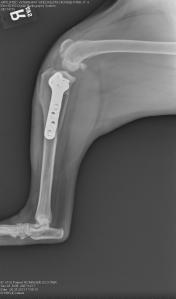

At surgery, bilateral cranial cruciate ligament ruptures were noted, along with bilateral medial meniscal tears. All those findings can be very painful for the patient. Both meniscal tears were debrided (removed) and bilateral tibial plateau leveling osteotomies (TPLOs) were performed. For more detailed information about ways we correct CrCL tears, please view that page on this website.

Right knee – note the joint swelling, arthritic changes, and forward movement of the tibia in relation to the femur.